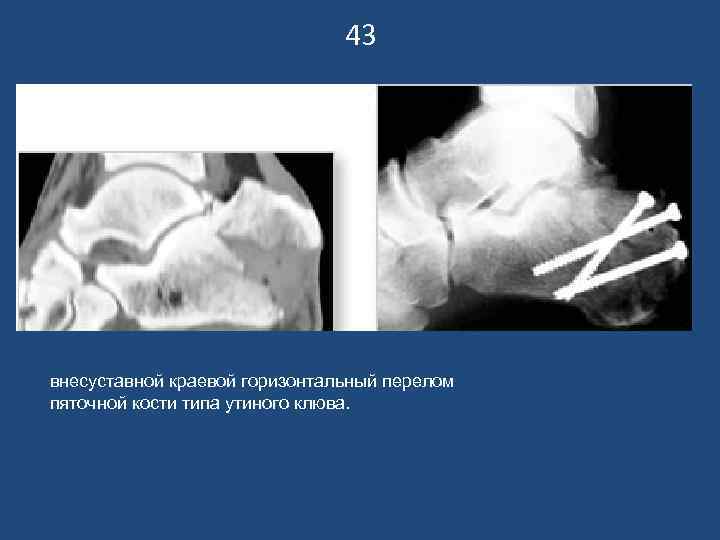

43 внесуставной краевой горизонтальный перелом пяточной кости типа утиного клюва.

42 Сочетанная травма. Внесуставной краевой горизонтальный перелом пятки типа утиного клюва слева. Компрессионный перелом+ краевой пятки справа. Компьютерная томография – компрессионные переломы L 1 -Th 12 позвонков